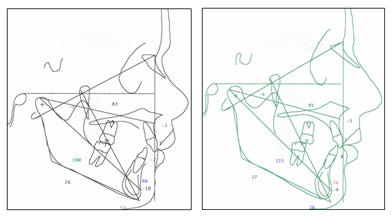

CEFALOGRAMAS DEL PACIENTE: Ricketts - Jarabak |

|

Fig.

5.- Cefalograma del paciente según Ricketts y Jarabak. |

Las medidas

cefalométricas revelaron un ángulo SNA de 83º, un SNB de 77.8 y un

ANB de 5.2º, el ángulo interincisivo tiene 137º, y el incisivo

inferior en relación a APg. Esta a -2 mm, la Base Craneal Posterior

muy grande 41 mm. (fig. 5 y en cefalogramas presentados al final de

esta descripción, antes y al final del tratamiento)